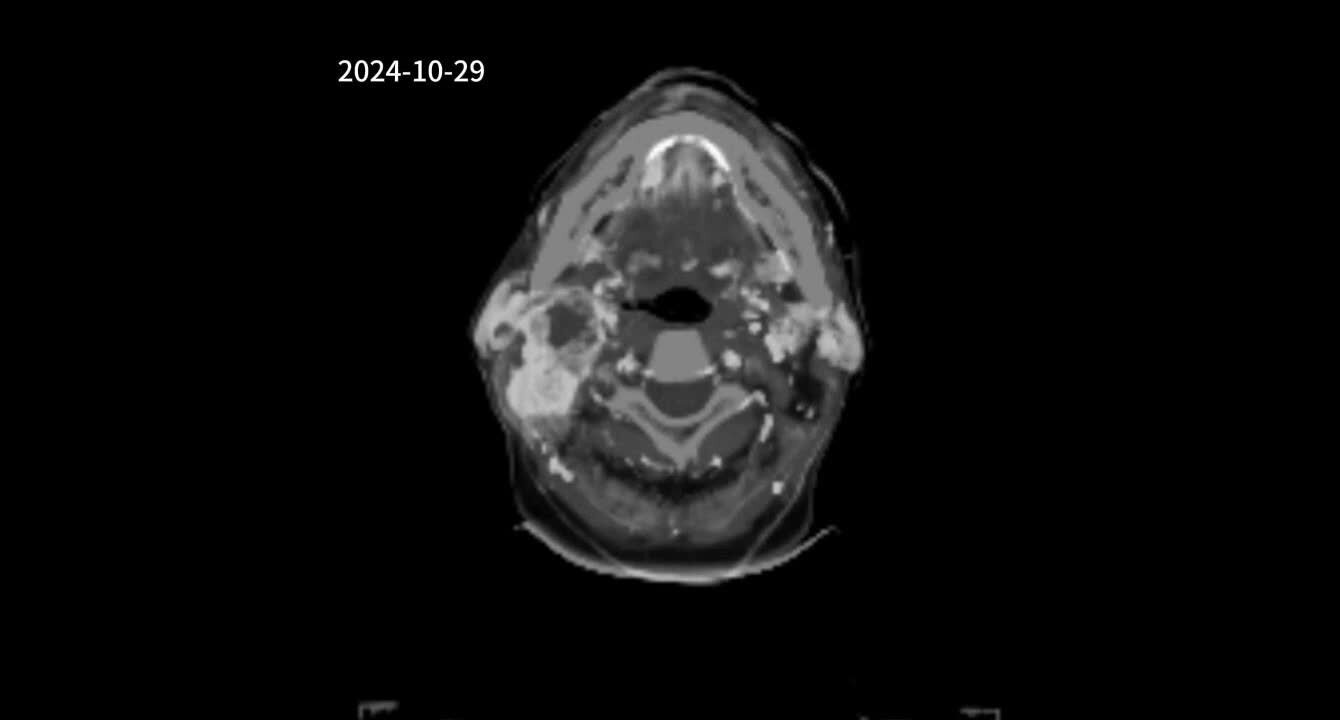

跨声门癌 喉癌同时侵犯声 门上中下区,粘 膜下生长,喉镜 检查常阴性

喉癌的ct,mri诊断ppt

声门型喉癌的ct分析